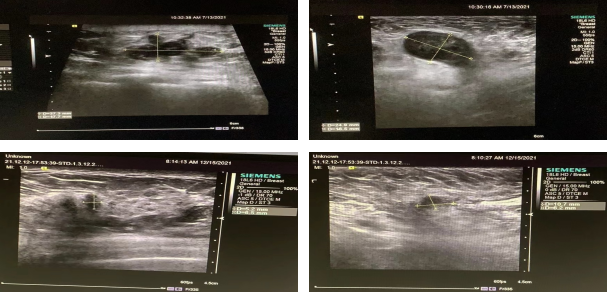

乳腺彩超示(2021-08-27):右乳房7:00距离乳头约4.8cm,距离皮肤约0.9cm探及低回声团块,大小约1.7*1.0*1.3cm,形态不规则,内示多枚强回声,纵横比<1,内血流信号不明显,超声弹性成像质地偏硬(4分)。右侧腋窝多发低回声结节,最大约2.4*1.5cm,内示血流信号。提示右乳肿瘤缩小明显,治疗方案疗效确切,疗效评估PR。继续按既定方案执行6周期化疗。

彩超示(2021-12-15):右乳房7:00距离乳头约5.2cm,距离皮肤约1.4cm探及低回声团块,大小约0.5*0.7*0.5cm,形态不规则,边界不清晰,纵横比<1,血流信号不明显。右侧腋窝探及淋巴结声像,淋巴门存在,皮髓质分界清,大小约1.1*0.6cm,皮质稍厚。

图5.2021-07-20彩超图(上)vs2021-12-15彩超图(下)